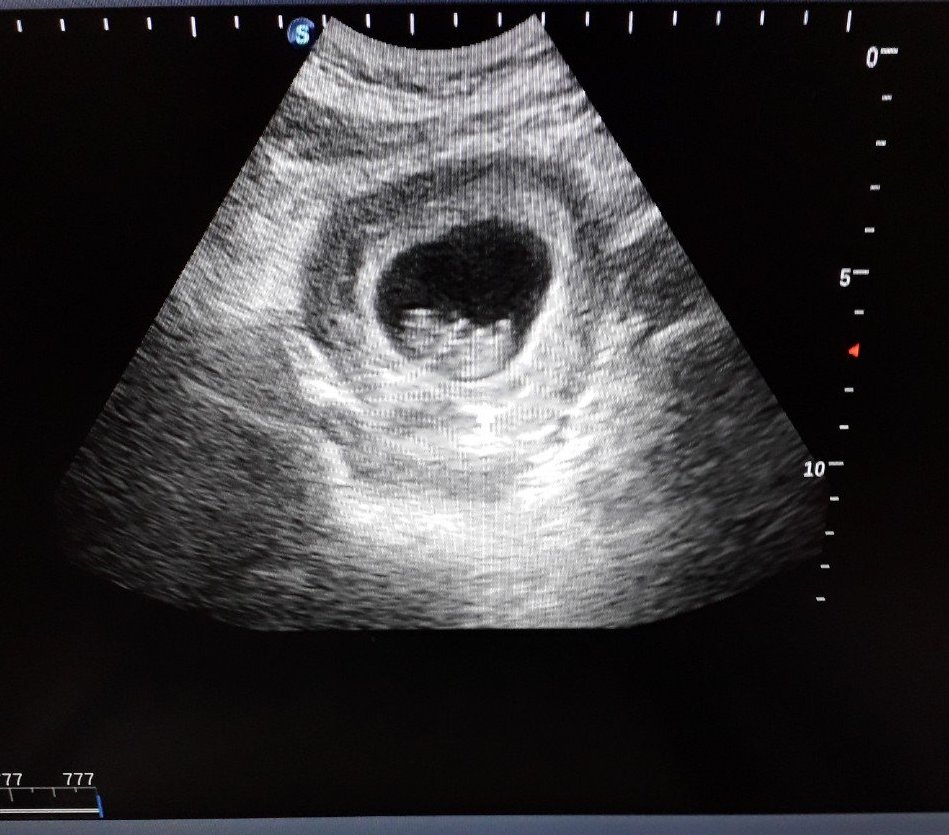

Ранният скрининг е неинвазивна процедура, провеждана между 11-та и 14-та седмица от бременността, която има за цел да идентифицира ранните признаци на различни вродени заболявания при плода. Процедурата включва два основни компонента: ултразвуково изследване и кръвни изследвания. Ранният скрининг, известен още като ранна феталнa морфология, е ултразвуково изследване, което оценява развитието на бебето и изключва възможни аномалии. Това изследване се извършва между 11-13 седмица от бременността и включва измерване на нухалната гъвкавост, оценка на кръвния поток през пъпната връв и оценка на риска от синдром на Даун и други синдроми.